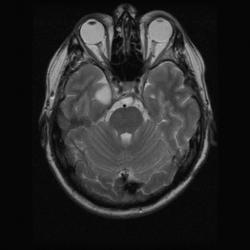

Извиняюсь за оффтопик, у меня сегодня пациент тоже обследовался по другому поводу, на желчный пузырь не жаловался. И не желтый.

Изображение Изображение Изображение Изображение

Всегда любил смотреть как выглядят камни жёлчного пузыря на МРТ. Чёрные дыры вселенной... Клёвый